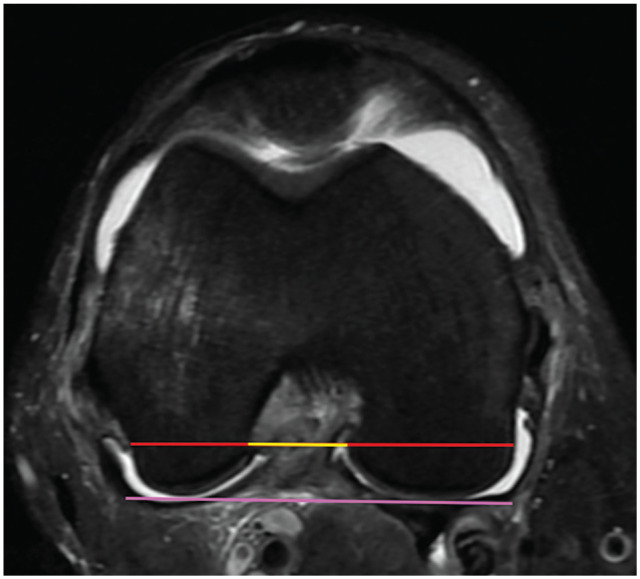

Methods: Patients ≥14 years of age with a confirmed ACL injury on MRI were included for review. Two orthopaedic resident physicians measured the NWI using both axial and coronal cuts using previously described measurement criteria as well as a modification utilizing the MRI cuts with the widest bicondylar width. The NWI was computed and a t test was performed to compare the axial and coronal measurements. Interobserver reliability was assessed using 2-way mixed intraclass correlation coefficients (ICCs).

Results: A total of 64 patients with ACL injuries were included. Modified axial and coronal NWIs for the cohort were a mean ± SD of 0.27 ± 0.02 and 0.23 ± 0.02, respectively. Modified axial NWIs were greater than coronal NWIs (P < .001). Standard axial and coronal NWIs for the cohort were 0.29 ± 0.03 and 0.25 ± 0.03, respectively. Standard axial NWIs were greater than coronal NWIs (P < .001). Modified axial and coronal NWIs for male and female patients were not different (P = .61 and P = .14, respectively). Axial notch width measurements were greater than coronal notch widths for both modified and standard measurements (P < .001). Axial intercondylar distances were not different from coronal intercondylar distances for both standard and modified measurements (P = .06 and P = .22, respectively). The ICCs for modified coronal and axial NWIs were 0.88 and 0.97, respectively. The ICCs for standard coronal and axial NWIs were 0.99 and 0.99, respectively.

Conclusion: NWIs were greater when measured on an axial MRI compared with the coronal plane for both measurement methods. This was because notch widths were measured wider in this plane since intercondylar distances were not statistically different.